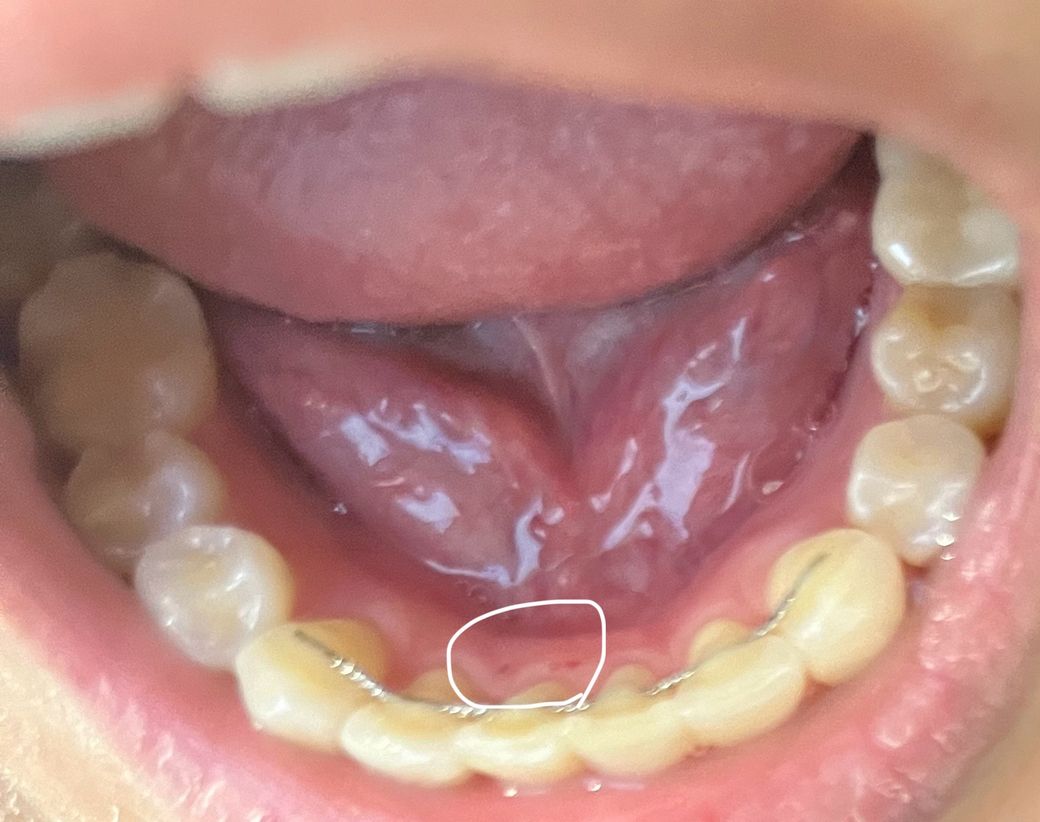

잇몸 안쪽에 이런 상처같은게 있는데 구내염인가요?

흐릿해서 잘 안보이는것 같긴한데 안쪽에 상처가 있습니다 이거 구내염일까요? 언제 생긴건지 모르겠습니다ㅠ

사진에 보이는 상처는 구내염이 아니라 그냥 단순 상처 인거 같습니다. 시간이 지나면 괜찮아 지실꺼에요.

입안쪽에 상처가 생긴 것으로 보이며, 크게 문제가 되어보이지는 않으며, 시간이 지남에 따라 아물 가능성이 높습니다. 헥사메딘 가글액과 같은 소독용 가글액 사용이 염증이 덧나는 것을 예방할수 있습니다.

사진상 구내염 혹은 양치 시 상처가 생긴 정도로 보이며 며칠 이내로 사라질 것으로 예상됩니다.